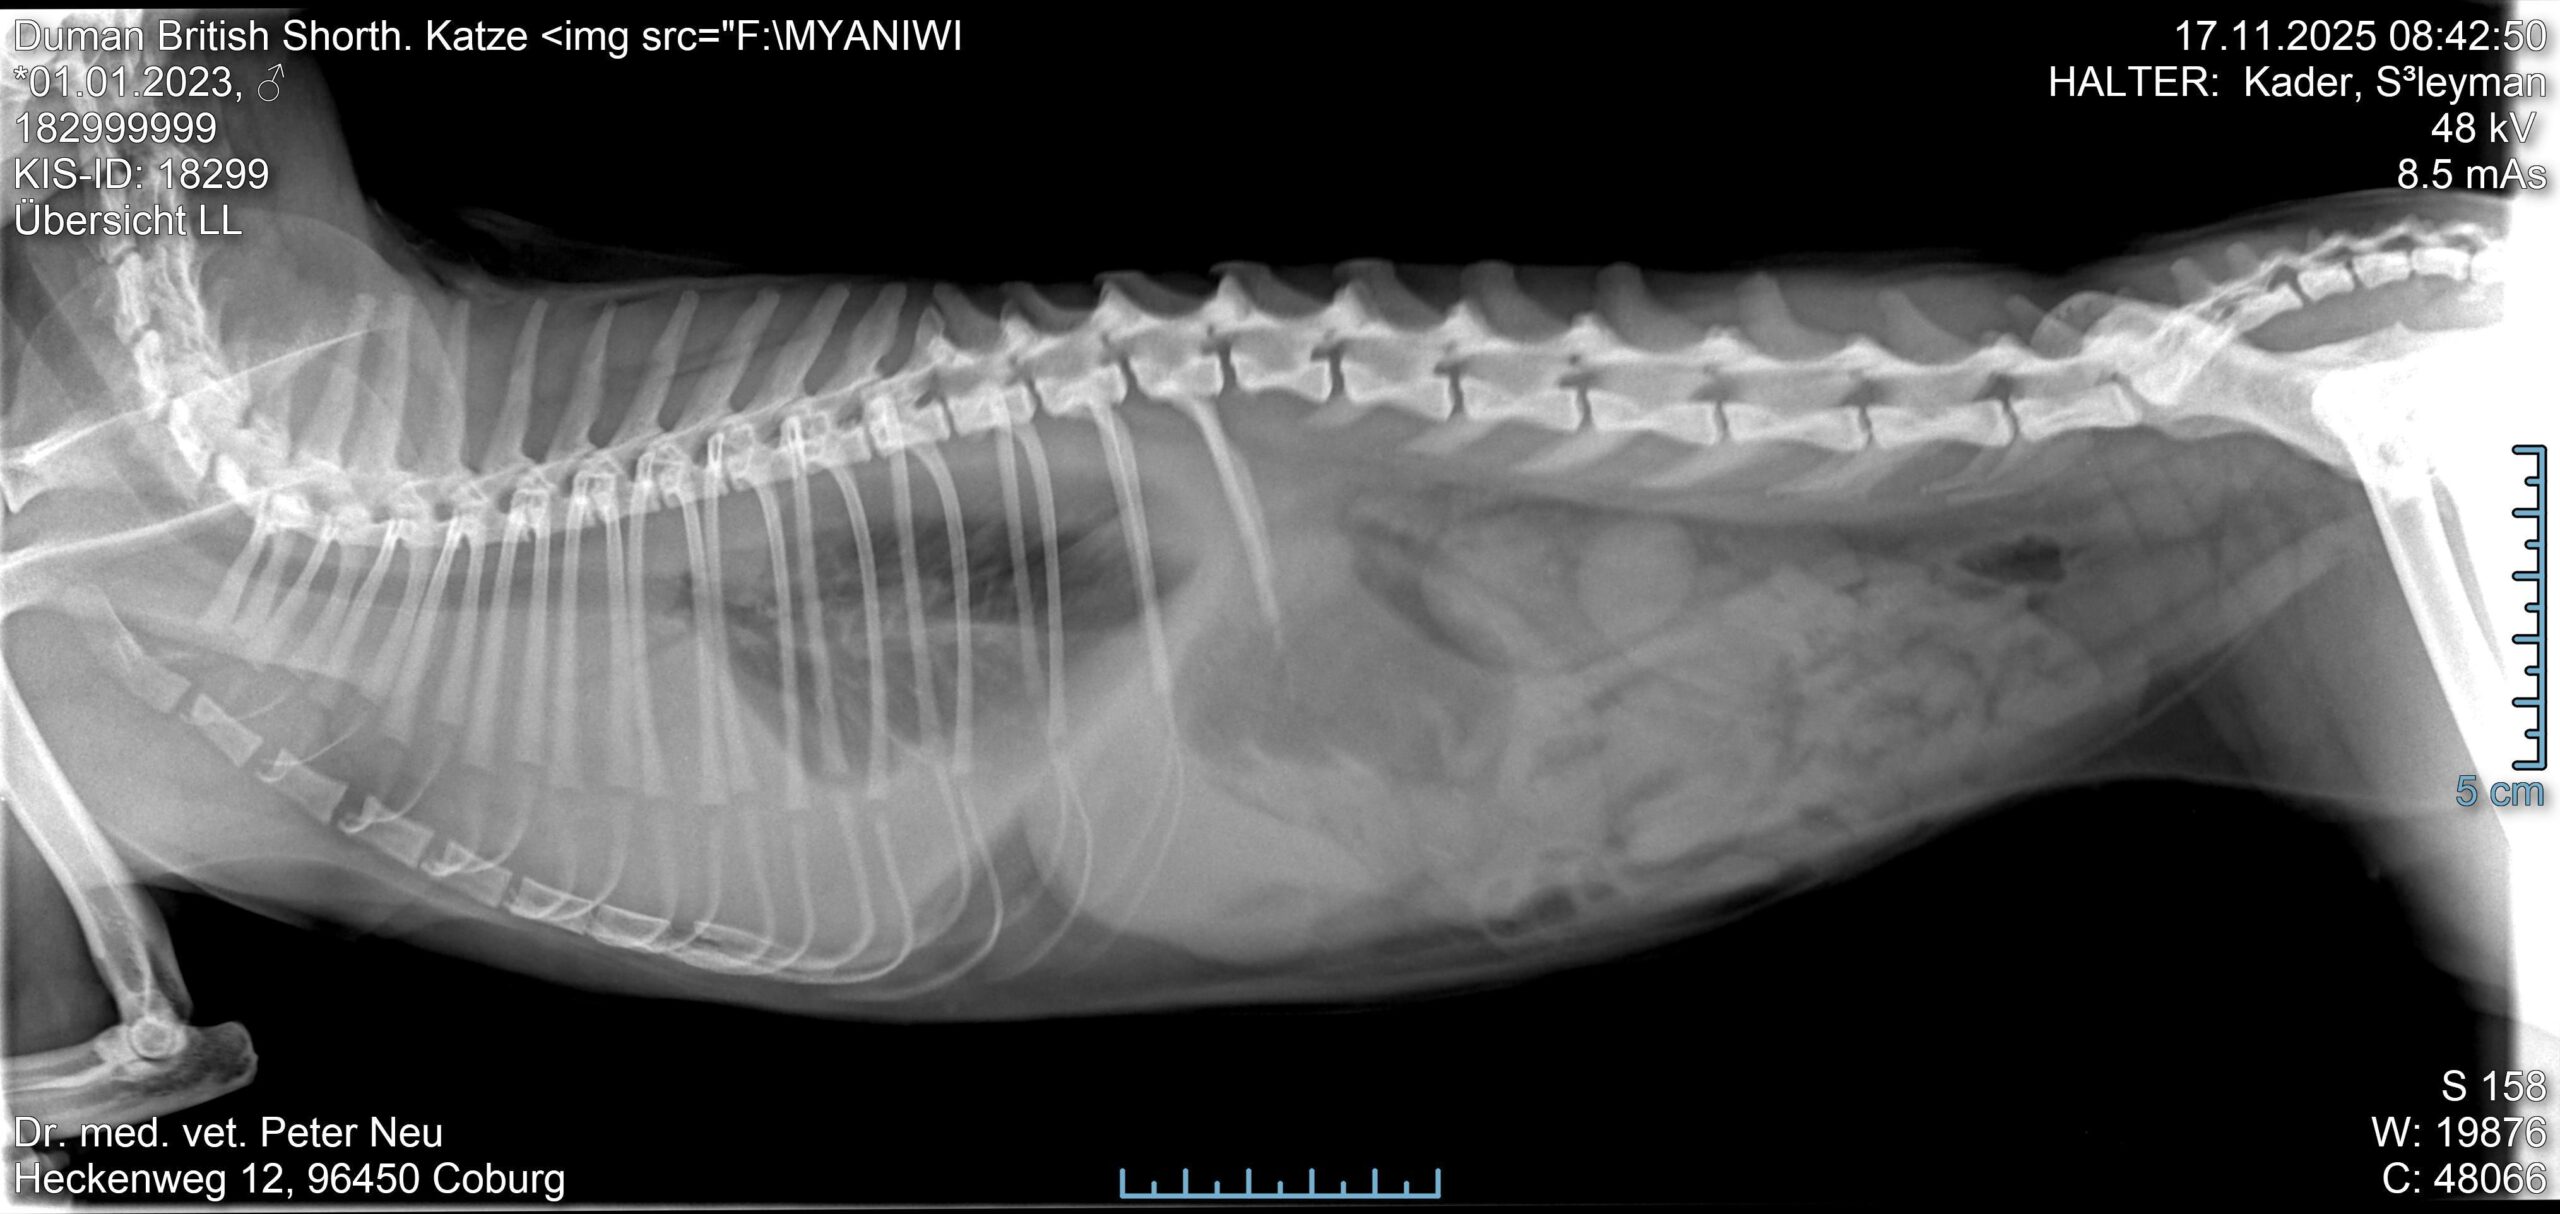

Mir persönlich hat sie sehr weitergeholfen, als ich eine 2 jährige Katze untersucht habe, bei der mir bei der Untersuchung auffiel, dass sie etwas angestrengt atmete. Ein Röntgen war schnell gemacht, es lag eindeutig ein Pleuralerguss vor. Das Tier war aber fieberfrei und eigentlich noch bei gutem Allgemeinbefinden.

Danach haben wir den Erguss punktiert und auf der linken Seite ca 80 ml einer gelblichen leicht trüben Flüssigkeit mit Spritze und Dreiwegehahn abgezogen. Danach war auch gleich die Atmung des Tieres besser.